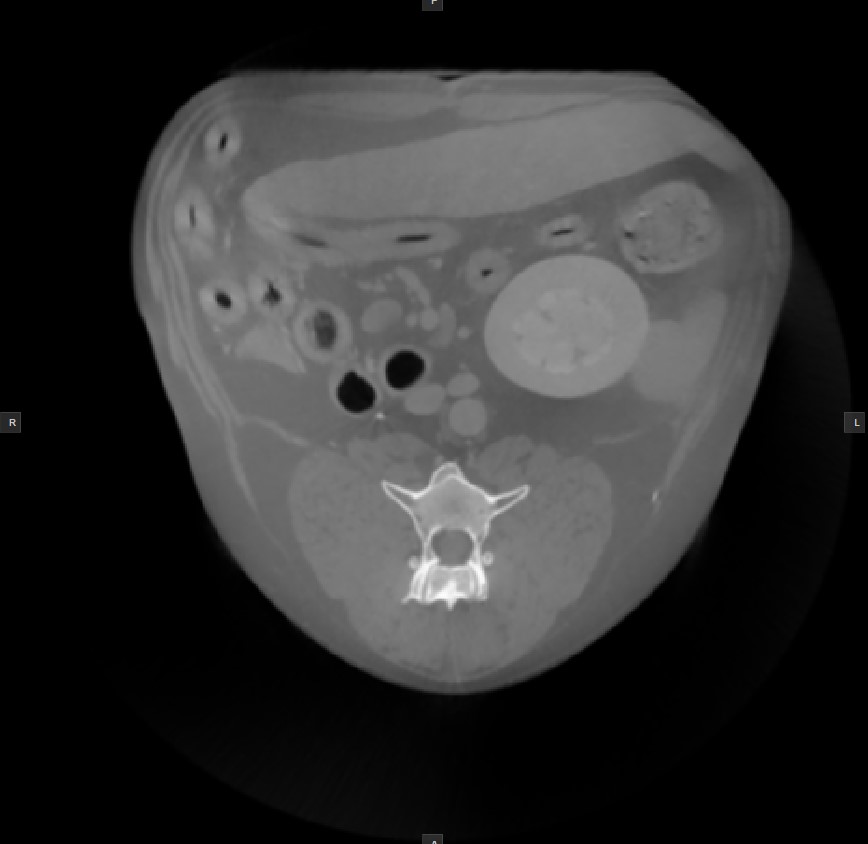

Histogram¶

A windowing histogram is a graphical representation of the distribution of intensity values in an image. It displays the number of pixels at each intensity level, allowing users to adjust the brightness and contrast by setting a window around a range of intensity levels. By adjusting the position and width of the window, the user can optimize the image for their specific needs and better visualize the image features.

To change the window width, press and drag the left or right edge of the rectangular area representing the window.

To change the position or the window center, press and hold on the rectangular area and drag in the desired direction.

Invert Image¶

The process of inverting the dark pixels into light pixels and vice versa in an image based on the DICOM standard is called inverting the polarity of the image.